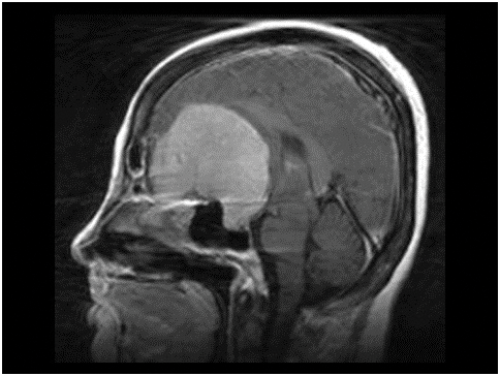

Figure 6: MRI of brain showing huge olfactory groove meningioma.

The name of this rare syndrome is well known to ophthalmologists but they may not be aware of its origin or true nature. It was described in 1911 [2] by Robert Foster Kennedy (1884-1952), who was born in Belfast and became Professor of Neurology at Cornell University, New York, but the condition had been noted as early as 1893 by Sir William Gowers, another famous British Neurologist. The syndrome consists of ipsilateral optic atrophy and contralateral optic disc oedema resulting from a brain tumour in the frontal lobe of the brain, usually an olfactory groove meningioma (Figure 6). Such a lesion must first compress its adjacent optic nerve and later cause raised ICP because the axons in an already atrophic ON cannot develop axoplasmic flow stasis, swell, compress the blood vessels and produce disc oedema.